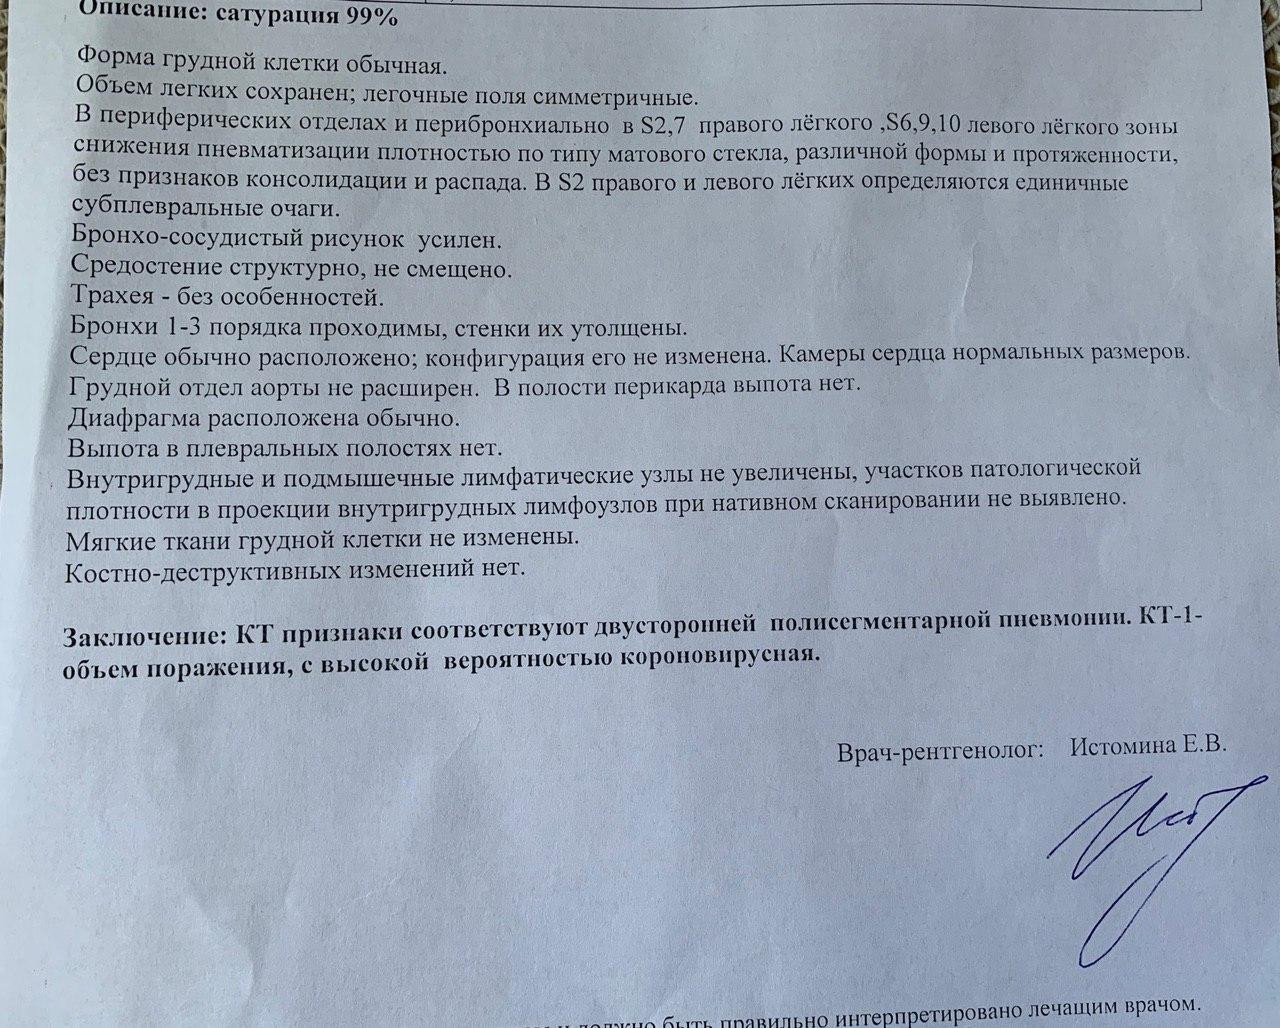

Острая внебольничная пневмония по МКБ-10: признаки и примеры